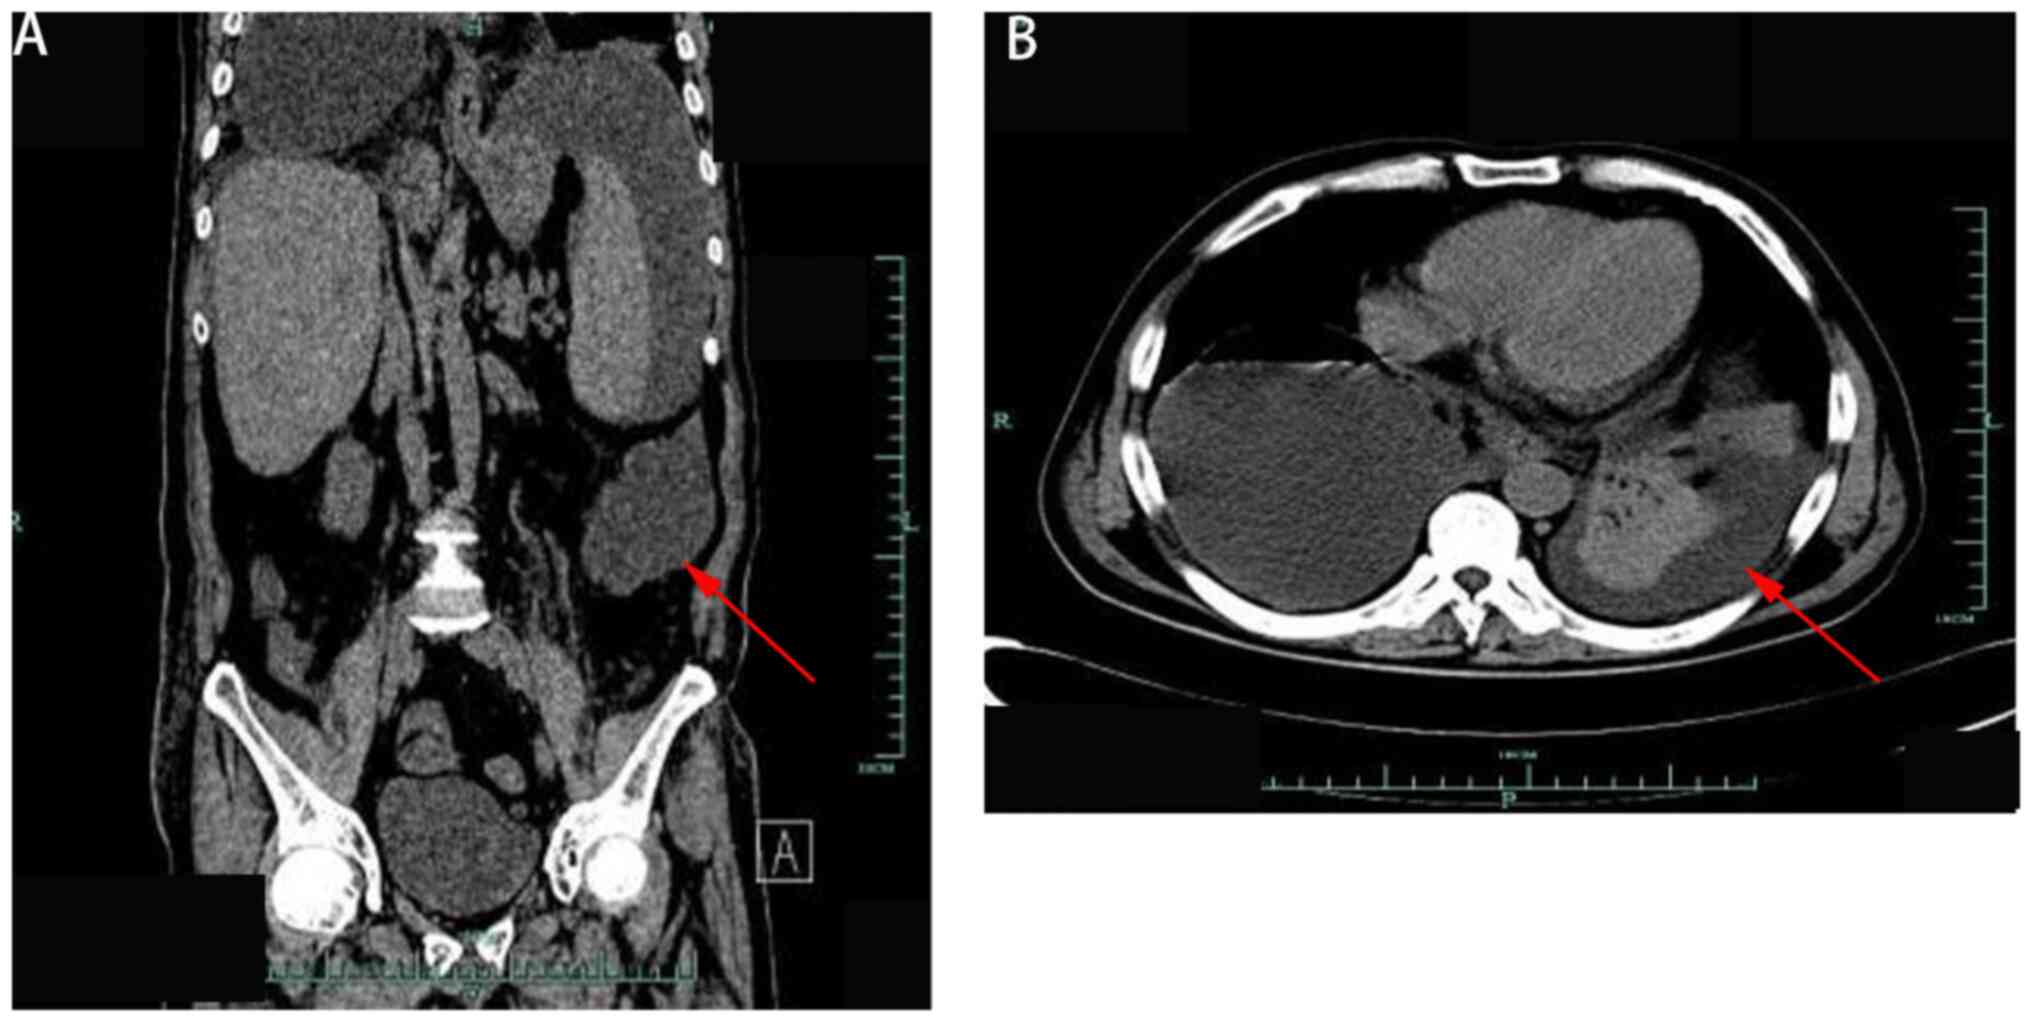

A 51-year-old man with gastric torsion and transverse colon redundancy underwent gastric reduction and fixation, along with partial resection of the transverse and descending colon, at a local hospital in June 2015 (Minle County Traditional Chinese Medicine Hospital, Zhangye, China). On postoperative day 5, discharge of fecal and foul purulent fluid from the upper abdominal incision, abdominal distension and colonic anastomotic leakage were observed. On the 7th post-operative day an ileostomy was performed (Minle County Traditional Chinese Medicine Hospital). After 2 weeks of hospitalization, the patient's condition did not improve, and they were transferred to Hexi University Affiliated Zhangye People's Hospital (Zhangye, China). On admission, a physical examination was conducted and showed a temperature of 38.8˚C (normal range, 36.1-37.0˚C), pulse rate of 118 beats/min (normal range, 60-100 beats/min), respiratory rate of 25 breaths/min (normal range, 16-20 breaths/min) and blood pressure of 110/70 mmHg. The abdomen was slightly distended, with a 16-cm longitudinal incision visible in the middle and upper abdomen, and a 6-cm wound opening in the upper segment. Purulent exudation with a foul odor was observed deep in the abdominal cavity. During exploration using the fingers, the colon anastomosis opening was reached, and contact was made with the titanium nail and an overflow of a significant amount of purulent fluid. In the lower abdomen, a longitudinal wound measuring 7 cm was observed, requiring intermittent suture removal due to local infection, with a visible drainage tube in the lower abdomen. Additionally, a small intestinal stoma, measuring 4 cm in diameter, was noted in the right lower abdomen. The skin around the stoma showed erosive erythema and inflammation, with a diameter of ~8 cm. An abdominal drainage tube was visible in the lower left abdomen, with a slight discharge of purulent fluid. Auscultation revealed diminished bowel sounds, while palpation indicated concave edema in both lower limbs. Computed tomography confirmed the presence of an abdominal abscess (Fig. 1).

Figure 1

Computed tomography examination of abdominal abscess formation. (A) Sagittal plane and (B) coronal plane.